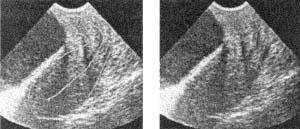

Рис. 17 a. HAF-AV. Чрезмерный передний перегиб матки. Трансабдоминальное сканирование при опорожненном мочевом пузыре.

Рис. 17 б. NF-AV. При наполненном мочевом пузыре перегиб матки практически устраняется. Трансабдоминальное сканирование. a б